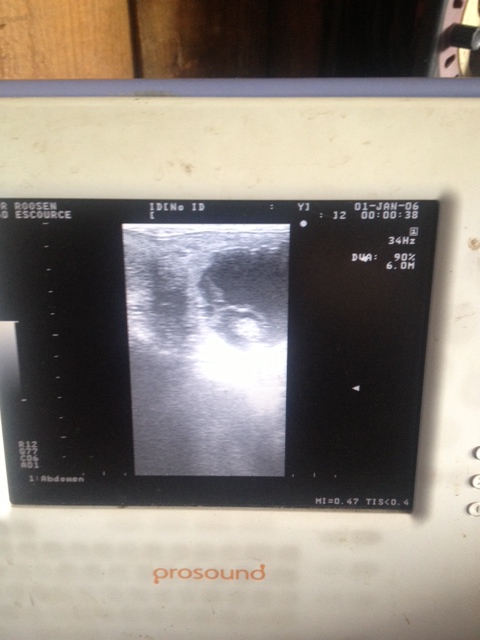

| Dire merci | Mouè, je ne sais pas, je vais attendre comme tu dis. Sinon, bonne nouvelle, Dové va être papa!! ![]() ![]() |

Par lilou : le 17/06/14 à 14:35:04

| Dire merci | Oui, Vecchio, une trèèès bonne nouvelle, j'ai un peu pris un risque, en achetant un étalon très cher sans même être sûre qu'il était fertile Là je suis rassurée ![]() |